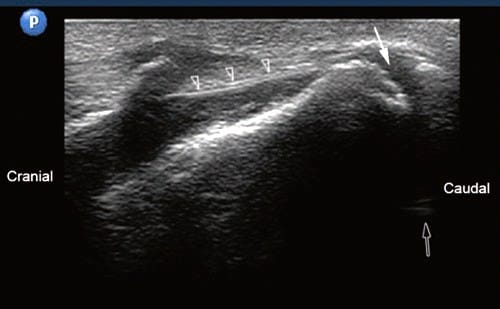

With the patient in the prone position, the sacral hiatus is palpated, and a linear high-frequency transducer (or curved low-frequency transducer in obese patients) is placed transversely in the midline to obtain a transverse view of the sacral hiatus as described in the course Caudal Block. The transducer is then rotated 90° to obtain a longitudinal view of the sacral hiatus and the coccyx (Fig. 1.1). The first cleft caudal to the sacral hiatus is the SCJ.

After local anesthesia infiltration of the skin and subcutaneous tissue, a 22- to 25-gauge needle is advanced into the SCJ under real-time ultrasonography. We use an out-of-plane approach while adjusting the needle’s path to match the angulation of the SCJ cleft to allow for a traumatic needle insertion (Fig. 1.2). The needle is advanced slightly through the SCJ cleft, and usually, loss of resistance is felt, indicating placement of the needle tip anterior to the ventral sacrococcygeal ligament. Lateral fluoroscopy may be obtained to confirm the depth of the needle and to monitor the spread of the injectate.